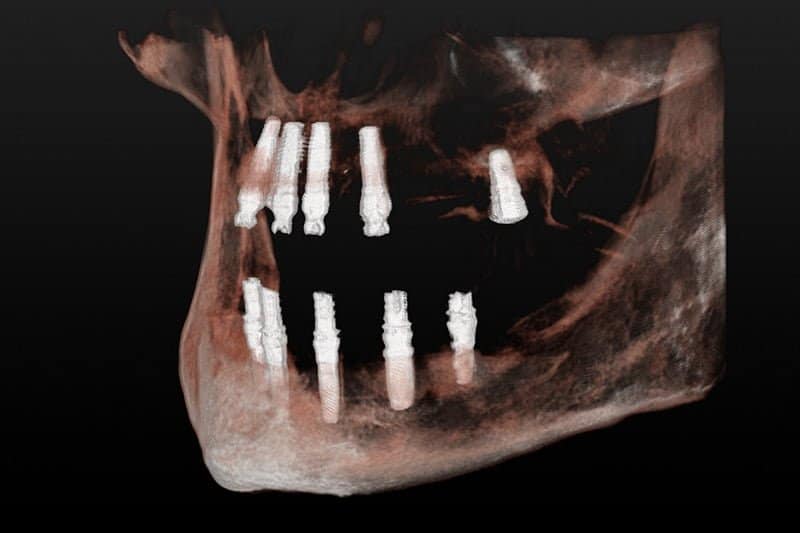

La solución que planteamos para resolver su caso fue una rehabilitación total, en una sola sesión y bajo sedación. Retirando todos los dientes afectados por la periodontitis y los implantes antiguos en mal estado, y colocando en una sola sesión implantes nuevos y saneando todos los tejidos, en el mismo día le colocamos la nueva prótesis fija provisional. Cuando los tejidos curaron y maduraron pudimos terminar con las prótesis definitivas de alta estética.